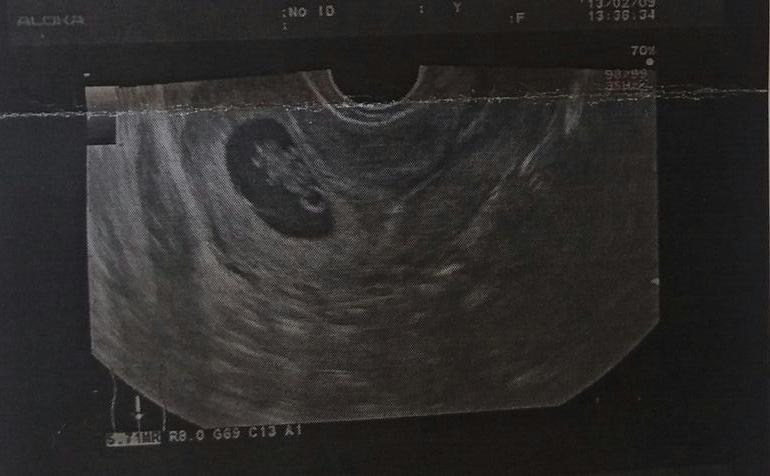

УЗИ, КТГ, доплерПервая Б 2013г - срок по М 7нед и5дней. По УЗИ -7нед3дня. КТР -11мм) девочка)

Вторая Б 2017г- срок по М 7нед 4дня. По УЗИ -7нед.5дней. КТР -14мм. Кто там, естественно пока не знаем, но муж предположил мальчишку, раз больше - значит мальчик. Мужская логика😅